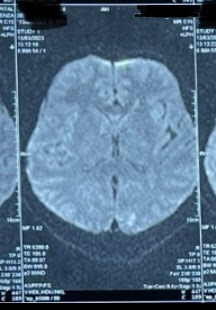

MRI:

Provisional diagnosis:

Cerebrovascular accident

With acute infarct in left internal capsule

With acute infarct in left occipital lobe